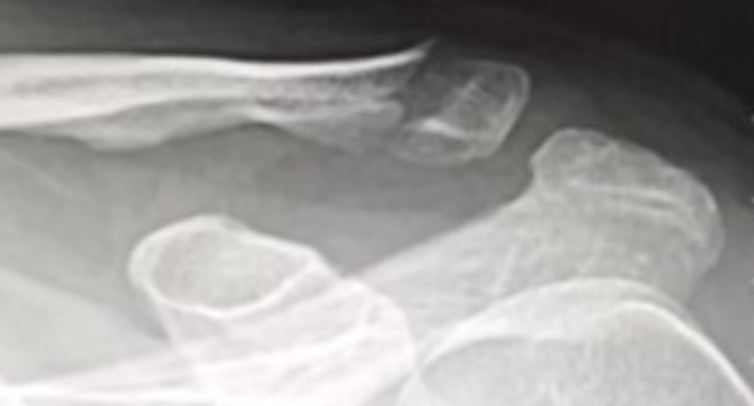

골절 사고 3주 후 엑스레이 영상. 드디어 골진이 나와서 벌어진 틈을 메우고 있다.